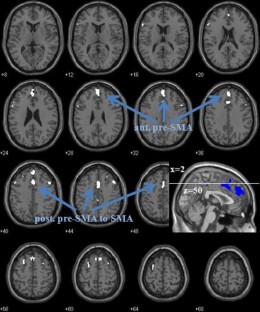

Aging is known to be associated with changes in cerebral morphometry and in regional activations during resting or cognitive challenges. Here, we investigated the effects of age on cerebral gray matter (GM) volumes and fractional amplitude of low-frequency fluctuation (fALFF) of blood oxygenation level-dependent signals in 111 healthy adults, 18–72 years of age. GM volumes were computed using voxel-based morphometry as implemented in Statistical Parametric Mapping, and fALFF maps were computed for task-residuals as described in Zhang and Li (Neuroimage 49:1911–1918, 2010) for individual participants. Across participants, a simple regression against age was performed for GM volumes and fALFF, respectively, with quantity of recent alcohol use as a covariate. At cluster level p < 0.05, corrected for family-wise error of multiple comparisons, GM volumes declined with age in prefrontal/frontal regions, bilateral insula, and left inferior parietal lobule (IPL), suggesting structural vulnerability of these areas to aging. FALFF was negatively correlated with age in the supplementary motor area (SMA), pre-SMA, anterior cingulate cortex, bilateral dorsal lateral prefrontal cortex (DLPFC), right IPL, and posterior cingulate cortex, indicating that spontaneous neural activities in these areas during cognitive performance decrease with age. Notably, these age-related changes overlapped in the prefrontal/frontal regions including the pre-SMA, SMA, and DLPFC. Furthermore, GM volumes and fALFF of the pre-SMA/SMA were negatively correlated with the stop signal reaction time, in accord with our earlier work. Together, these results describe anatomical and functional changes in prefrontal/frontal regions and how these changes are associated with declining inhibitory control during aging.

Fig. 3